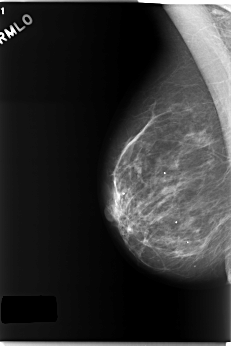

C_0218_1.RIGHT_MLO

RIGHT_MLO LINES 5872 PIXELS_PER_LINE 3920 BITS_PER_PIXEL 12 RESOLUTION 50 NON_OVERLAY